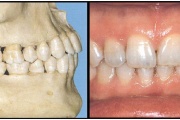

Ravijärgne seis. Jäävhammas on täielikult lõikunud.

) Röntgenülesvõte. Ülemise esimese jäävmolaari lõikumine on takistatud 2. piimamolaari tõttu

Esimese jäävmolaari ektoopiline lõikumine